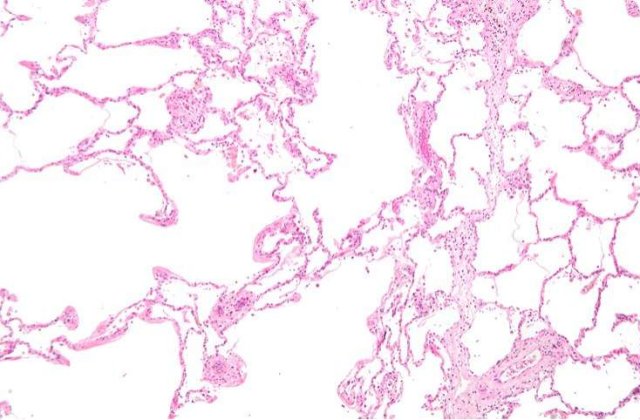

Aceste celule pulmonare sunt capabile sa se regenereze si sa formeze si apoi sa se integreze in structuri biologice multiple ale plamanului, precum bronhiole, alveole si capilare pulmonare, a precizat acelasi medic, potrivit MEDIAFAX.

Aceste celule au fost injectate apoi unor soareci ai caror plamani erau afectati. Cercetatorii au constatat ca celulele introduse puteau sa se reproduca pentru a crea noi bronhiole, alveole si capilare pulmonare, capabile de a se integra in structura tesuturilor existente ale plamanilor acelor soareci.